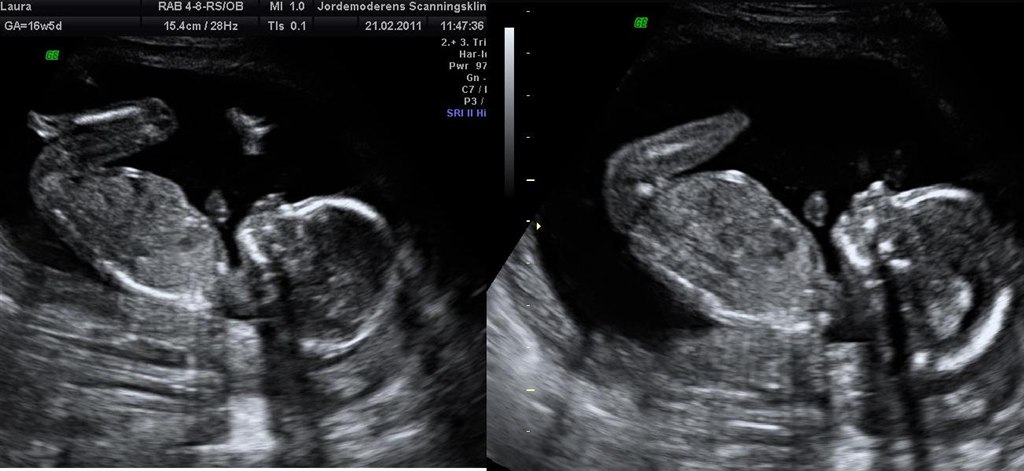

Tillykke med den lille pige!

Præcis sådan så det også ud til min misdannelsesscanning, og jordemoderen var helt sikker på, at det er en pige der gemmer sig.

Nu må vi se om hun havde ret om 10 ugers tid. Jeg må indrømme at jeg er frygter lidt at hun kan have taget fejl (ikke at jeg ikke vil have en dreng, men nu har man jo købt lidt lyserødt tøj osv.). Man ved jo ikke om pungen og tappen måske kan have gemt sig..